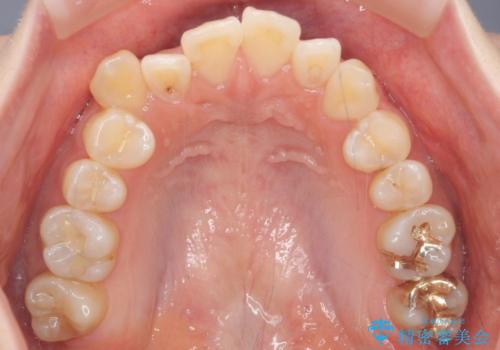

今回は口元も出ていないうえに、右上のみの八重歯のため奥歯を後ろに下げて治療しました。

右上の犬歯をおろしてくるのに、顎間ゴムを使用しています。